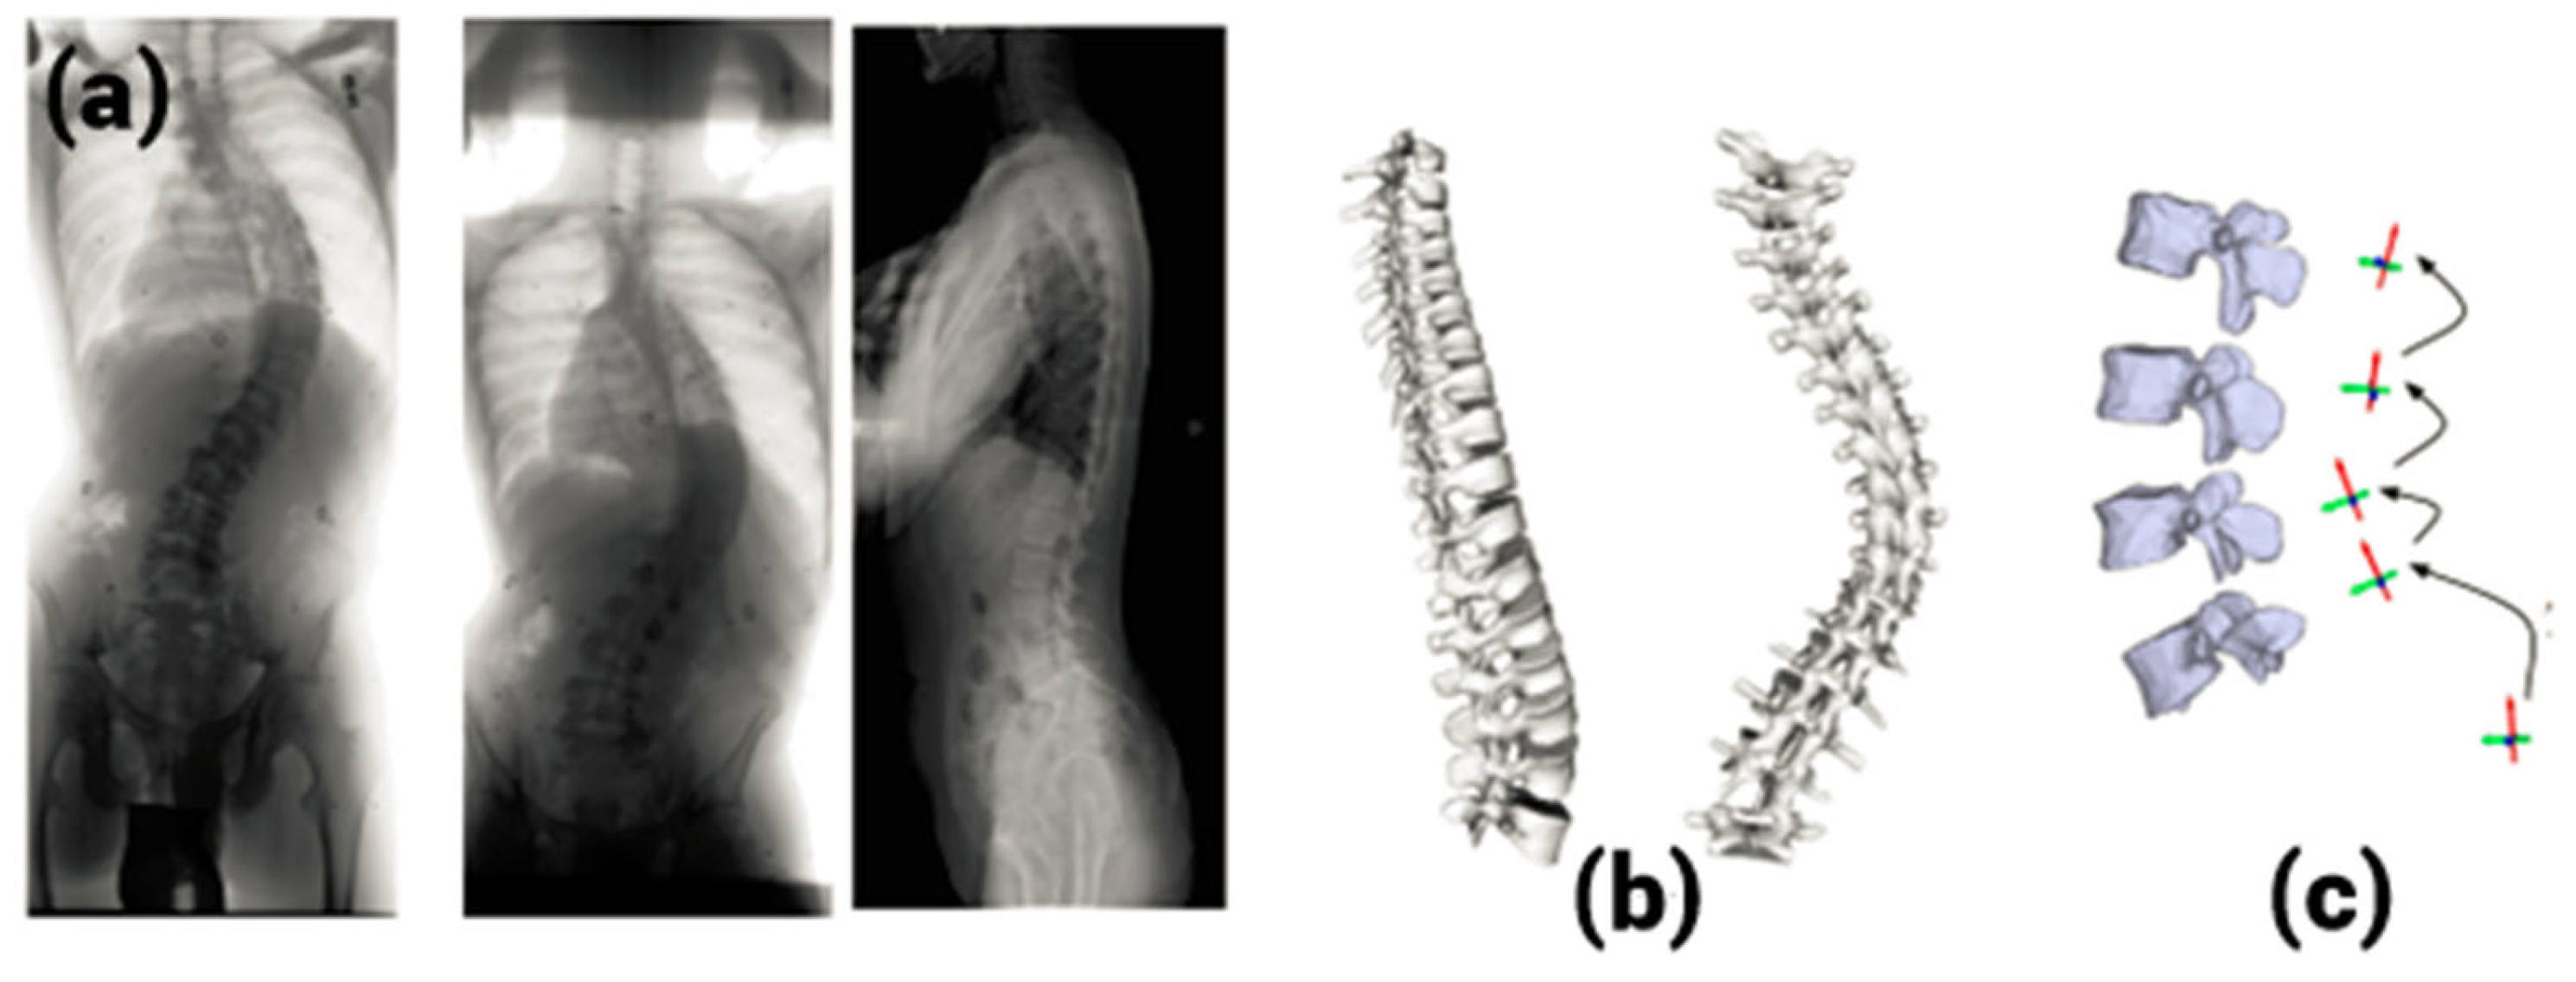

2. 3D Reconstruction from Multiplanar Radiographs

The 3D reconstruction of human ribcages from multiplanar radiographs was the first attempt of a method other than CT or MRI modelling methods [8,9]. Dansereau et al. [9] came up with a method based on three radiograph views: a postero-anterior view and a postero-anterior view with 20° leaning incidence and a lateral view. Figure 1 shows the entire process. This technique was time-consuming, as manual digitization was needed twice (on each postero-anterior view). Eleven points on the rib midlines, including five radio-opaque markers, needed to be identified on the radiographs. Since the process of digitization is manual, the technique was slow and dependent on the operator. Further, the third radiograph was obtained with a non-standard format. Makino et al. [10] tried to reconstruct the scoliotic spine using multiplanar images obtained from a CT scan. This method has limitations like a risk of high radiation dosage and nonstandard image formats. Hence, the method did not become popular, and researchers tried to get 3D reconstruction from only two radiographs.

Figure 1. A 3D reconstruction from multiplanar radiographs. (a) Radiographs in three views, (b) 3D reconstruction, (c) 3D reconstruction of vertebrae.